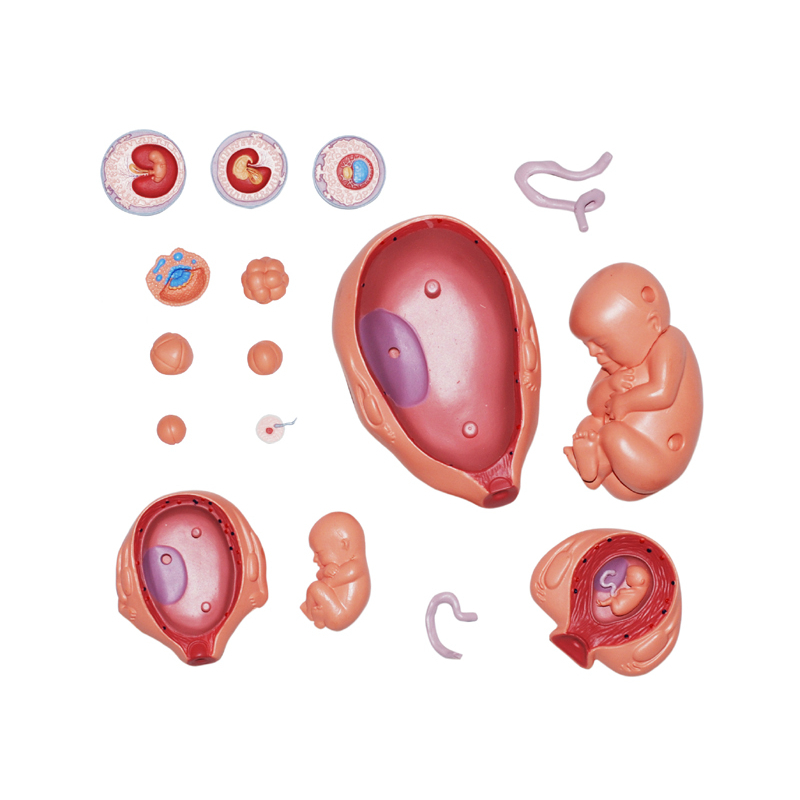

4D MASTER Human Anatomy Premium Embryo Development, Fertilisation to Fetus Development